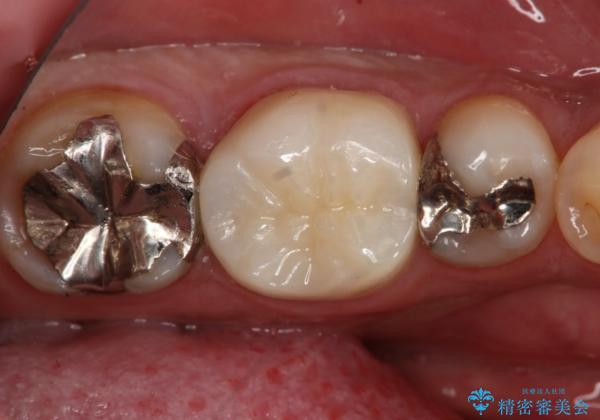

フルジルコニアクラウンによる銀歯のやり変え

- 左下6番の銀歯が不適であったためやり変えを勧めたところセラミックでの治療を希望された患者様です。

切削量などを考慮し、フルジルコニアクラウンでの治療を選択しました。

う蝕が深く切削量が多くなりましたが痛みなどは起きなかったので、予定通りフルジルコニアクラウンでの治療で進めました。